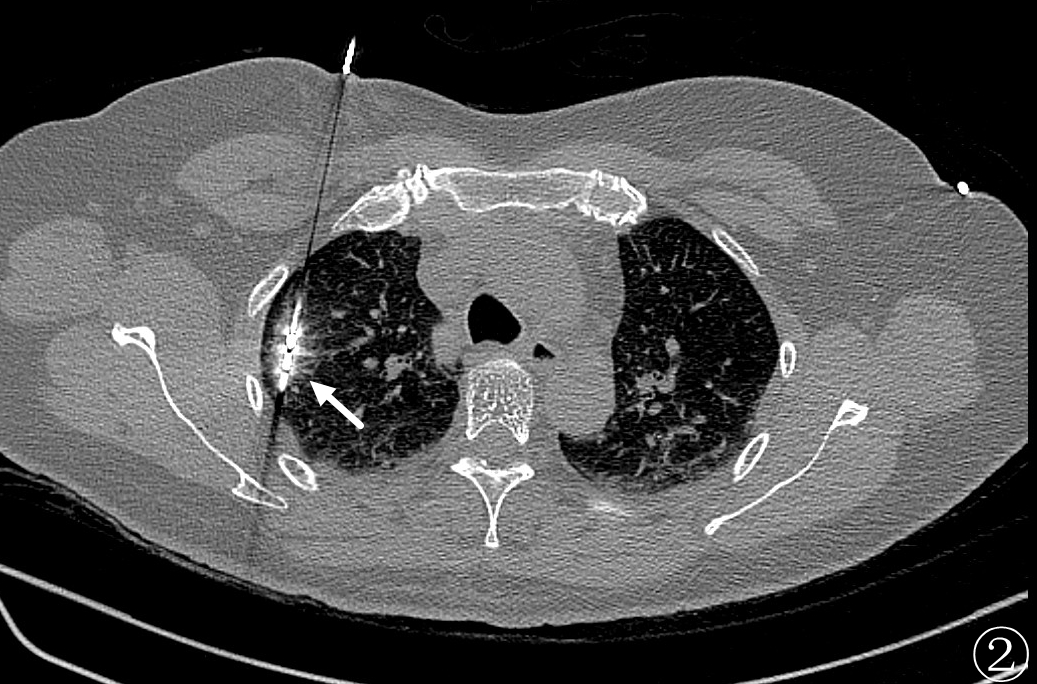

廖良忠主任带领廖健主治医师等介入团队,再与患者及家属充分沟通,征得患者同意后,行经皮肺穿刺活检同步微波消融术。

术前进行常规CT扫描确定消融区域及穿刺路径,局部麻醉后利用微波消融针,从体表定位点沿着穿刺路径逐层穿刺到达预定消融区域(图②),予以单次多点消融靶区,最后可见消融后靶区完全覆盖病变区域(图③、④)。手术过程仅耗时约1h,术中肺尖可见少量出血,未发现气胸及咯血等并发症,术后3天复查影像可见消融区完全覆盖病灶(图⑤),病人安然出院,从而达到治愈性消融的目的。